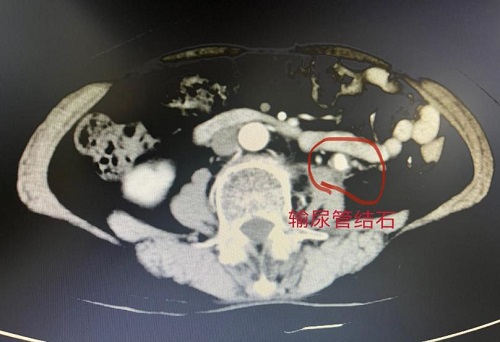

患者女,69岁, 11月10日来到我院泌尿与小儿外科治疗,入院后行CT,提示脓肾、左肾萎缩,左肾多发钙化,左侧输尿管上段多发结石,左肾周筋膜增厚。该患者左肾功能重度受损,主任冯勇军组织科室医务人员讨论,为患者选择左侧脓肾切除,一并切除左侧腰部窦道的最佳手术方式。11月15日下午,由冯勇军主任主刀,对唐婆婆实施手术,手术顺利完成。

此手术难度大:肾脏与周围组织粘连严重,且肾脏与腰部皮肤之间有慢性窦道形成,一直有脓性液体流出。术中见左侧腰部窦道从左侧腰部皮肤一延伸至左侧肾脏。左侧腰部皮肤及皮下组织与左侧肾脏、输尿管紧密粘连。左侧输尿管内有结石多枚,较大者约1.5cm。